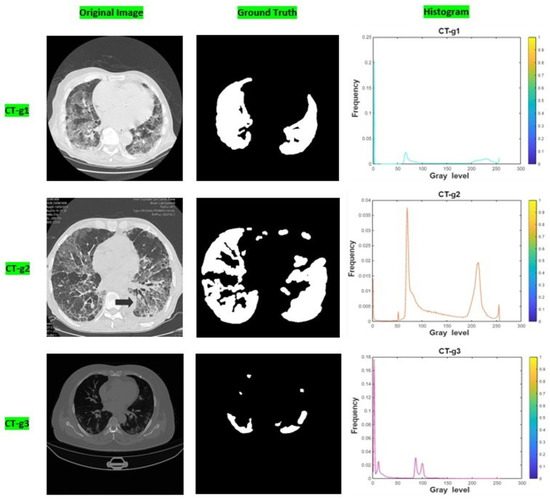

Levy Flight and Chaos Theory-Based Gravitational Search Algorithm for Image Segmentation

by Sajad Ahmad Rather and Sujit Das

Mathematics 2023, 11(18), 3913; https://doi.org/10.3390/math11183913 - 14 Sep 2023

Cited by 7 | Viewed by 2257

Image segmentation is one of the pivotal steps in image processing due to its enormous application potential in medical image analysis, data mining, and pattern recognition. In fact, image segmentation is the process of splitting an image into multiple parts in order to [...] Read more.

Image segmentation is one of the pivotal steps in image processing due to its enormous application potential in medical image analysis, data mining, and pattern recognition. In fact, image segmentation is the process of splitting an image into multiple parts in order to provide detailed information on different aspects of the image. Traditional image segmentation techniques suffer from local minima and premature convergence issues when exploring complex search spaces. Additionally, these techniques also take considerable runtime to find the optimal pixels as the threshold levels are increased. Therefore, in order to overcome the computational overhead and convergence problems of the multilevel thresholding process, a robust optimizer, namely the Levy flight and Chaos theory-based Gravitational Search Algorithm (LCGSA), is employed to perform the segmentation of the COVID-19 chest CT scan images. In LCGSA, exploration is carried out by Levy flight, while chaotic maps guarantee the exploitation of the search space. Meanwhile, Kapur’s entropy method is utilized for segmenting the image into various regions based on the pixel intensity values. To investigate the segmentation performance of ten chaotic versions of LCGSA, firstly, several benchmark images from the USC-SIPI database are considered for the numerical analysis. Secondly, the applicability of LCGSA for solving real-world image processing problems is examined by using various COVID-19 chest CT scan imaging datasets from the Kaggle database. Further, an ablation study is carried out on different chest CT scan images by considering ground truth images. Moreover, various qualitative and quantitative metrics are used for the performance evaluation. The overall analysis of the experimental results indicated the efficient performance of LCGSA over other peer algorithms in terms of taking less computational time and providing optimal values for image quality metrics. Full article

(This article belongs to the Section E1: Mathematics and Computer Science)

Show Figures

Graphical abstract